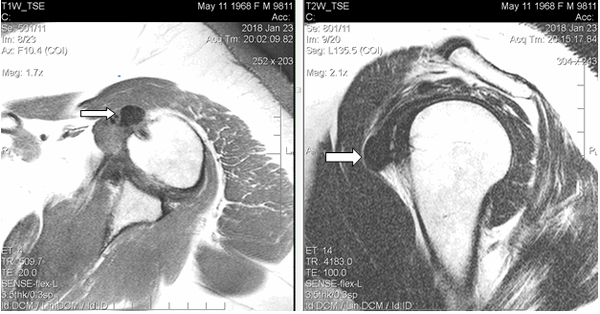

Результаты исследования и их обсуждение. При магнитно-резонансной томографии, (январь 2018 г.) в левом плечевом суставе выявлены умеренные дегенеративные изменения в виде краевых заострений суставной впадины лопатки, кальцинат в субдельтовидной сумке размерами 1,5х1,2 см, субхондральная киста акромиона диаметром до 0,4 см, небольшое количество выпота в субдельтовидно-субакромиальной сумке. Таким образом, МР-картина соответствовала акромиально-ключичному артрозу II стадии, плечелопаточному артрозу I стадии; выявлены субдельтовидно-субакромиальный бурсит, оссифицирующий капсулит плечевого сустава (рис. 1). Рекомендована консультация ортопеда.

Рис. 1. МРТ левого плечевого сустава пациентки Л., 49 лет (январь 2018 г.), Т1-ВИ, аксиальный срез (а) и Т2-ВИ, сагиттальный срез (б). В субдельтовидном пространстве в зоне отрога капсулы сустава вдоль сухожилия длинной головки на 9 часах условного циферблата головки плечевой кости визуализируется крупный кальцинат (обозначен стрелками) в виде гомогенно-гипоинтенсивного на Т1-ВИ и Т2-ВИ образования неправильно-округлой формы с четкими контурами размерами 1,5х1,2х1,1 см, без перифокального отека, деформирующий передний пучок дельтовидной мышцы